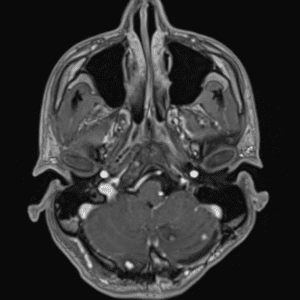

Case #5

Neurofibromatosis type II